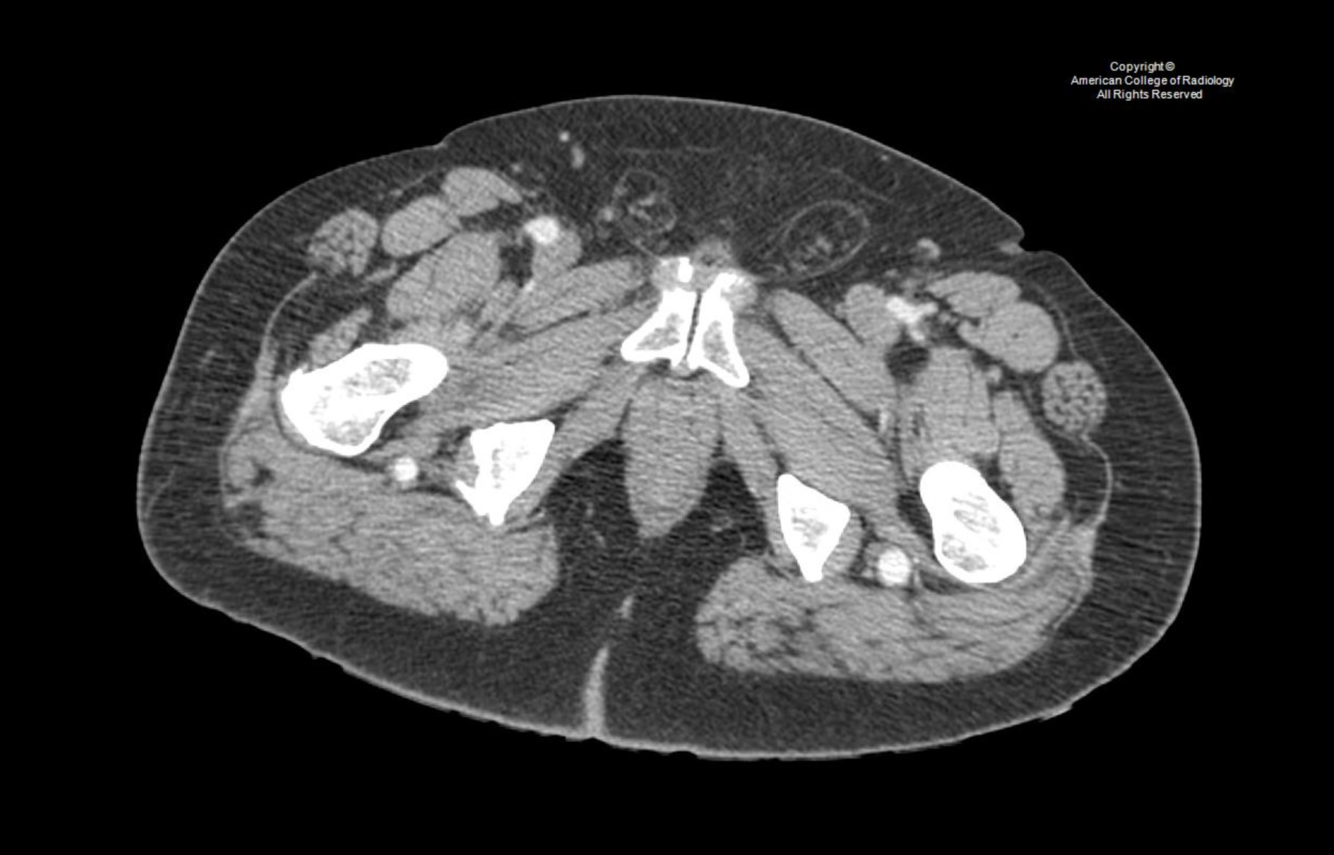

Distal aorta, iliac, pelvic & leg arteries: persistent sciatic artery: